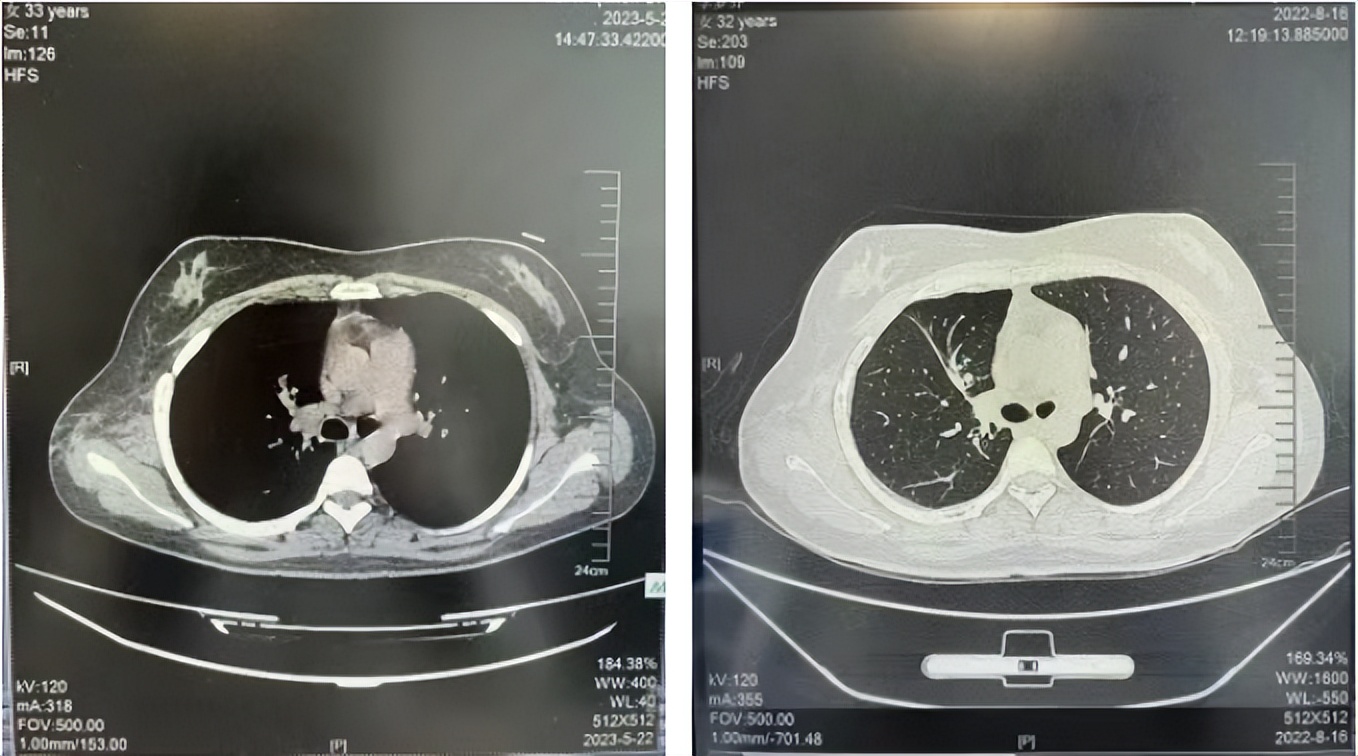

56岁,女性,无吸烟史饮酒史,既往体健。2023年02月患者体检发现肺占位性病变,胸部增强CT:右肺下叶后基底段结节;右侧锁骨上及纵隔内多发淋巴结肿大。PET-CT:右肺下叶周围型肺癌可能性大;1R、2L、3P、4R、4L及7组淋巴结转移可能性大。2023年02月就诊于本院胸外科行超声胃镜下纵隔肿物穿刺活检术,病理:结合免疫组化,符合肺腺癌。行NGS基因检测:EML4:exon20-ALK:exon20融合。PD-L1(克隆号22C3)TPS=55%。

临床诊断:右肺下叶恶性肿瘤cT1bN3M0,IIIB(第9版分期),纵隔淋巴结继发恶性肿瘤,锁骨上淋巴肿继发恶性肿瘤

治疗经过:2023年3月27日始行恩沙替尼靶向治疗至今,最佳疗效为PR,末次评效为维持PR。期间出现轻度肝功能异常(DILI 1级),对症处理后好转。截止目前PFS为26个月。

2023年2月20日基线检查

2024年6月复查PR(最佳疗效)

2024年12月复查维持PR

2025年3月复查维持PR